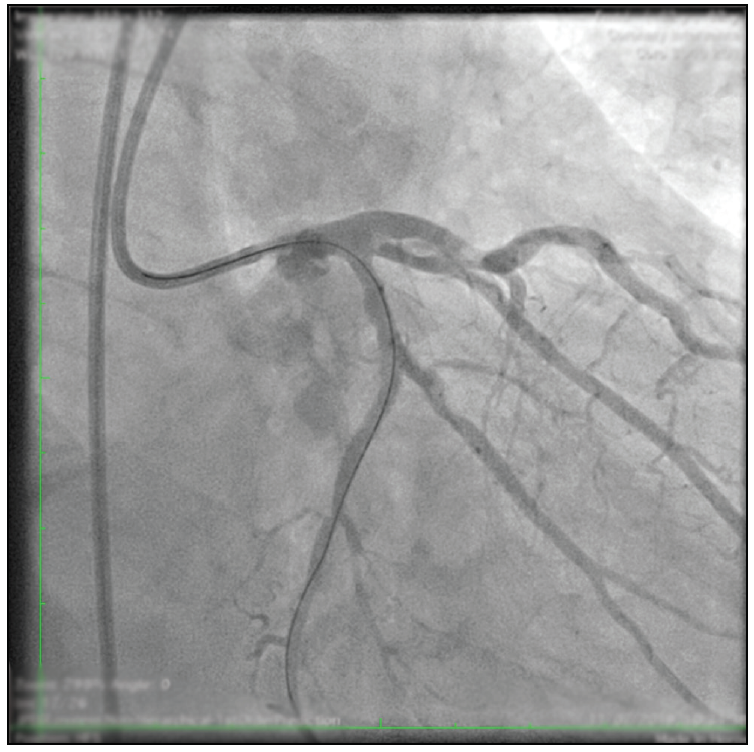

The procedure was continued by gaining support with a 6-F Guidezilla II extension. Predilations were alternatively done, in both branches, with semicompliant balloons (a 1.25- X 15-mm Tazuna [Terumo Europe] at 20 atm and then a 2.5- X 15-mm Tazuna at 18 atm) (Figure 3). The culotte technique was chosen considering the similar size of both branches and the presence of severe calcium. A Coroflex ISAR NEO stent (2.75 X 19 mm; B. Braun Melsungen AG) was advanced and implanted at 14 atm at the LCX across the OM1 ostium. Proximal optimization therapy was performed with a 3.5- X 8-mm NC Emerge balloon (Boston Scientific Corporation) at 12 atm. After regaining the OM1 access with a Sion guidewire (Asahi Intecc USA, Inc.), the stent struts were opened to the OM1 with a 2.5- X 15-mm Tazuna balloon at 10 atm (Figure 4) and a 3- X 32-mm Coroflex ISAR NEO stent was implanted at the OM1 (Figure 5).